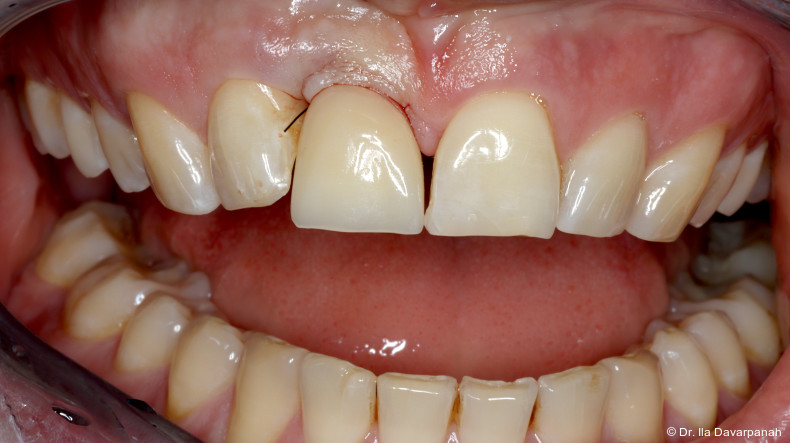

Postoperativ kam es trotz korrekter Implantatpositionierung und regelrechter Sofortversorgung zu einer Fraktur des Implantatkörpers im Bereich der Implantatschulter. Die radiologische Diagnostik mittels Röntgen und DVT zeigte ein Aufplatzen des Implantats im Übergangsbereich zwischen Konusverbindung und Implantatplattform. Das Frakturmuster deutete auf eine strukturelle Überlastung im hoch beanspruchten Schulterbereich hin. Implantatfrakturen stellen insgesamt eine seltene, jedoch für Patient und Behandler belastende Komplikation dar. Sie treten bevorzugt in Regionen mit erhöhten Biege- und Querkräften auf, insbesondere in der Frontzahnregion und bei frühzeitiger funktioneller Belastung.

Nach Entfernung des frakturierten Implantatkörpers erfolgte eine erneute Sofortimplantation mit einem alternativen Implantatdesign. Begleitend wurden Maßnahmen zur Stabilisierung von Hart- und Weichgewebe durchgeführt.

Die postoperativen Verlaufskontrollen zeigten stabile periimplantäre Verhältnisse ohne weitere Komplikationen. Die Osseointegration sowie die Weichgewebesituation stellten sich unauffällig dar.